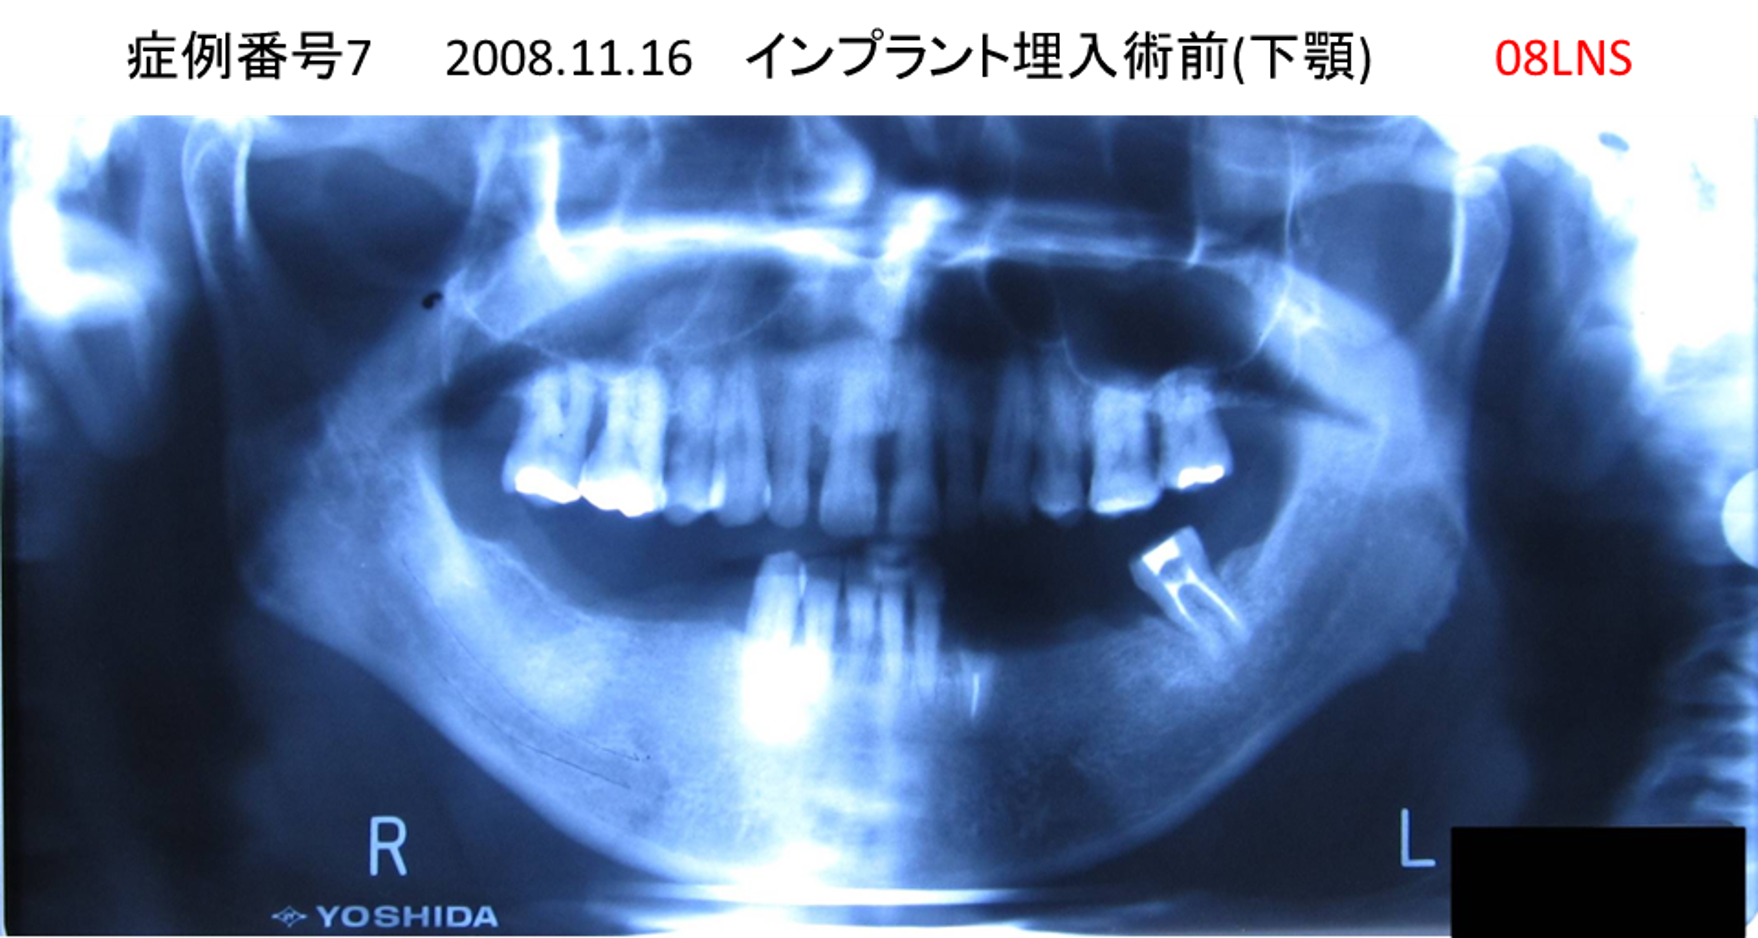

左下の奥歯が痛い患者様のインプラント症例

| 治療名称 |

インプラント |

| 治療費用 |

215万円+税 |

| 治療期間 |

5か月 |

| 患者さんの症状(主訴) |

左下の奥歯が痛い。 |

| 治療内容 |

| 治療結果 |

痛み無く、噛める。 |

| 治療の注意点(リスク/副作用) |

インプラントが壊れたら再治療が必要 |